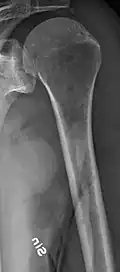

Multiple myeloma in the upper arm -

The diagnostic examination of a person with suspected multiple myeloma typically includes a skeletal survey. This is a series of X-rays of the skull, axial skeleton, and proximal long bones. Myeloma activity sometimes appears as "lytic lesions" (with local disappearance of normal bone due to resorption) or as "punched-out lesions" on the skull X-ray ("raindrop skull"). Lesions may also be sclerotic, which is seen as radiodense.[76] Overall, the radiodensity of myeloma is between −30 and 120 Hounsfield units (HU).[77] Magnetic resonance imaging is more sensitive than simple X-rays in the detection of lytic lesions. An MRI may supersede a skeletal survey, especially when vertebral disease is suspected. Occasionally, a CT scan is performed to measure the size of soft-tissue plasmacytomas. Nuclear Medicine Bone scans are typically not of any additional value in the workup of people with myeloma (no new bone formation; lytic lesions not well visualized on nuclear bone scan).

Humerus with multiple myeloma lesions -

Same humerus before, with just subtle lesions